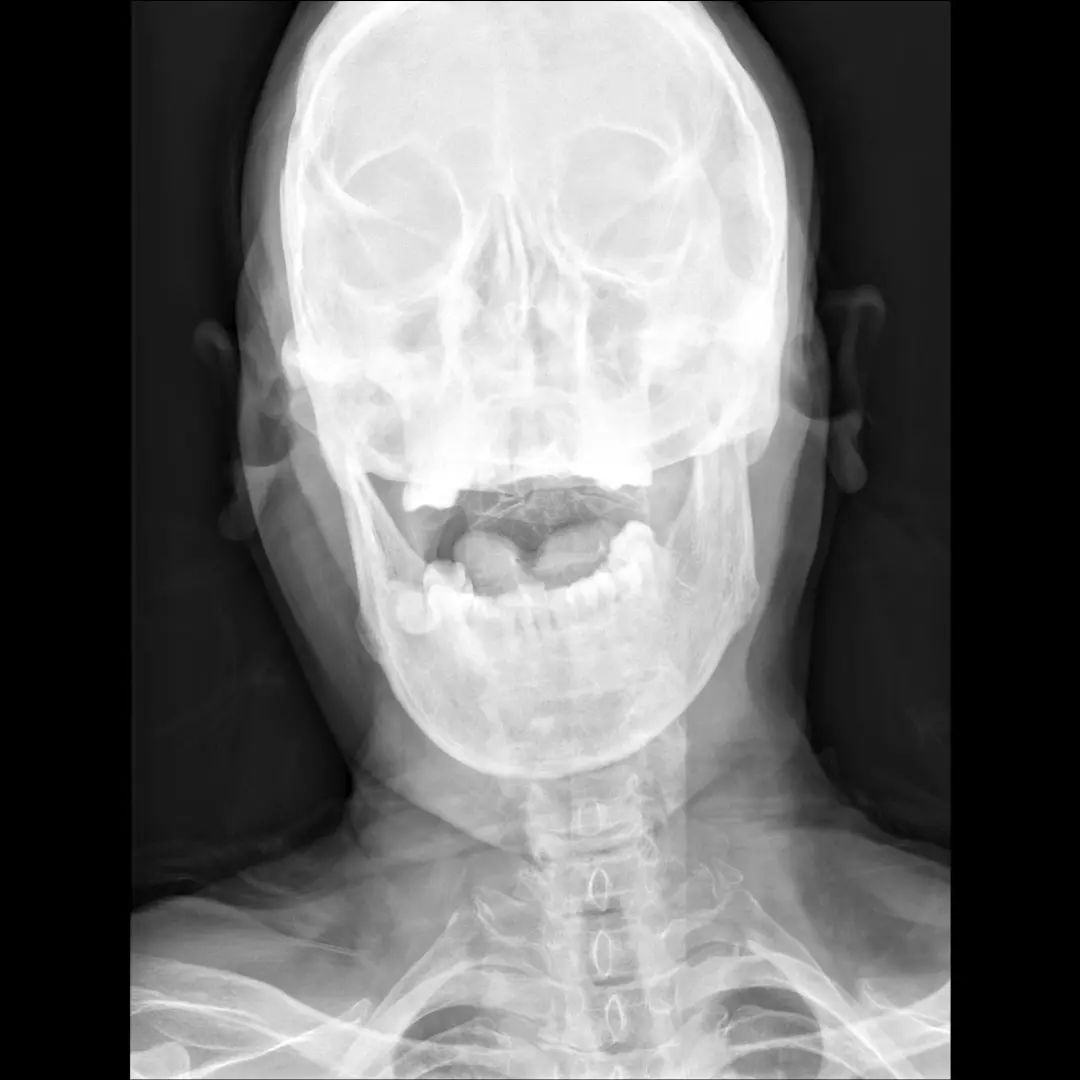

经过全程监护和系统治疗,患者术后恢复良好,骨折解剖复位,复查X线及CT显示固定位置佳,术后3天下地行走,术后4天即出院回家休养。

该手术为我市首例完成C1、2椎弓根钉棒系统固定手术,填补了枣庄在上颈椎外伤手术史上的空白,展现了枣庄市立医院脊柱外科不怕困难、勇于突破、积极向上的精神面貌,也是王存平主任技术高超、胆大心细的具体体现。